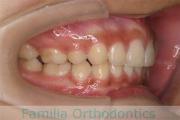

No.19V-044

- 上顎前突

- 13歳

- 女性

- 上:

- 44

- 下:

- 8558

- 主な使用装置:

- FEA

- 治療にかかった費用:

- 85万円

出っ歯を治したいということで小学生の時に来院されました。中学生になるまで経過観察をして、診断、上下左右から小臼歯を抜歯してマルチブラケット法にて治療を行いました。2年強、30回程度の通院が必要でした。

口元の突出感も大きく改善しています。

- ≫治療前

右側

正面

左側

上下とも前歯の叢生(でこぼこ、凹凸、ガタガタ)がありましたので、保定をしっかりやらないと後戻りのリスクが出てきます。